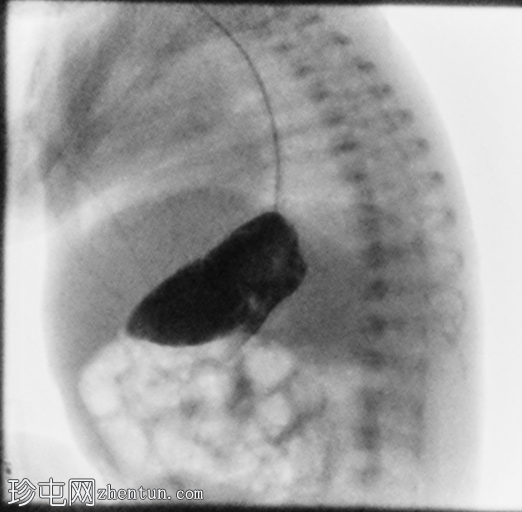

正位

3.png

侧位

4.png

定位片显示肠道气体分布无梗阻,经食管插管终止于右上腹。

胃位于右上腹。观察到轻度中段食管反流。造影剂在近端十二指肠的延迟通过量极少,这属于异常情况。

延迟正位和侧位X线片显示肠内容物通过时间极短。